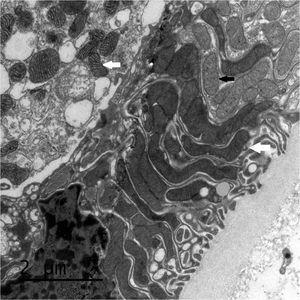

La biopsia renal del varón mostró ocho glomérulos: tres de ellos estaban esclerosados, dos presentaban lesiones de esclerosis segmentaria y focal con hialinosis y sinequia capsular (figura 1), otros dos marcada fibrosis capsular con ligera retracción del ovillo, y el restante un ligero incremento de la celularidad mesangial. El intersticio reveló atrofia tubular, fibrosis e infiltrado inflamatorio crónico. En las arteriolas se observó una intensa hialinosis subendotelial con marcada reducción luminal. La inmunofluorescencia mostró mínimo depósito inespecífico de IgM; y la ultraestructura, megamitocondrias con marcada distorsión de las crestas y aumento de la osmiofilia de la matriz interna a nivel podocitario (figura 2). En el segundo caso, inicialmente se obtuvo un único glomérulo para microscopía óptica sin hallazgos relevantes, salvo una mínima esclerosis arteriolar. Se realizó una nueva biopsia cinco años después en la que se obtuvo un cilindro con ocho glomérulos ópticamente normales (figura 3). En la microscopía electrónica destacaba, igual que en el primer caso, la presencia de mitocondrias de gran tamaño con distorsión de las crestas y con una matriz interna desestructurada en los podocitos, con ausencia de laminación de la membrana basal glomerular, así como focos con adelgazamiento de esta, observándose de forma focal zonas con desaparición de pedicelos (figuras 4 y 5), no obstante, y debido a la heteroplasmia, también es posible ver mitocondrias de aspecto normal (figura 6)

Figura 1. Glomeruloesclerosis focal y segmentaria.

Figura 2. Microscopía electrónica. Megamitocondrias podocitarias con marcada distorsión de las crestas y aumento de la osmiofilia de la matriz interna.

Figura 5. Microscopio electrónico. Podocito con megamitocondrias (flechas blancas) y mitocondrias normales (flecha negra).